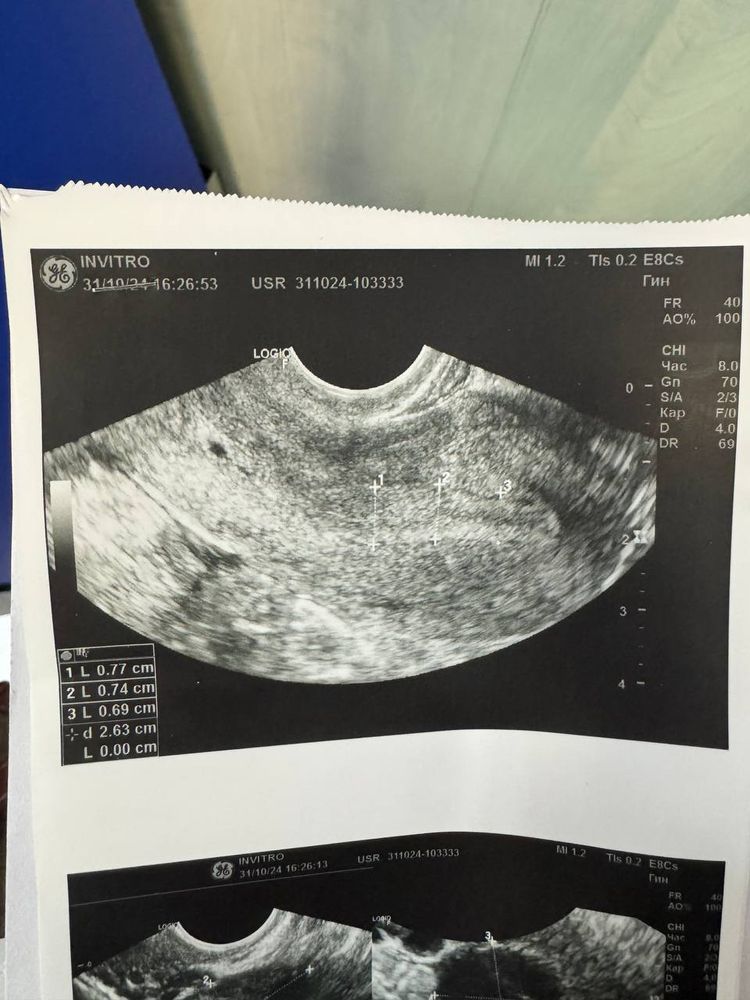

ЖТ нормальное или нет

Девочки,нужна ваша помощь. У меня всегда овуляция на 18ДЦ. Сходила на 17 ДЦ на узи и врач сказала что видно хорошое ЖТ и такое ощущение что овуляция была два дня тому назад. Очень странно мне показались снимки,скажите пожалуйста нормальное ли ЖТ смущает белая линия